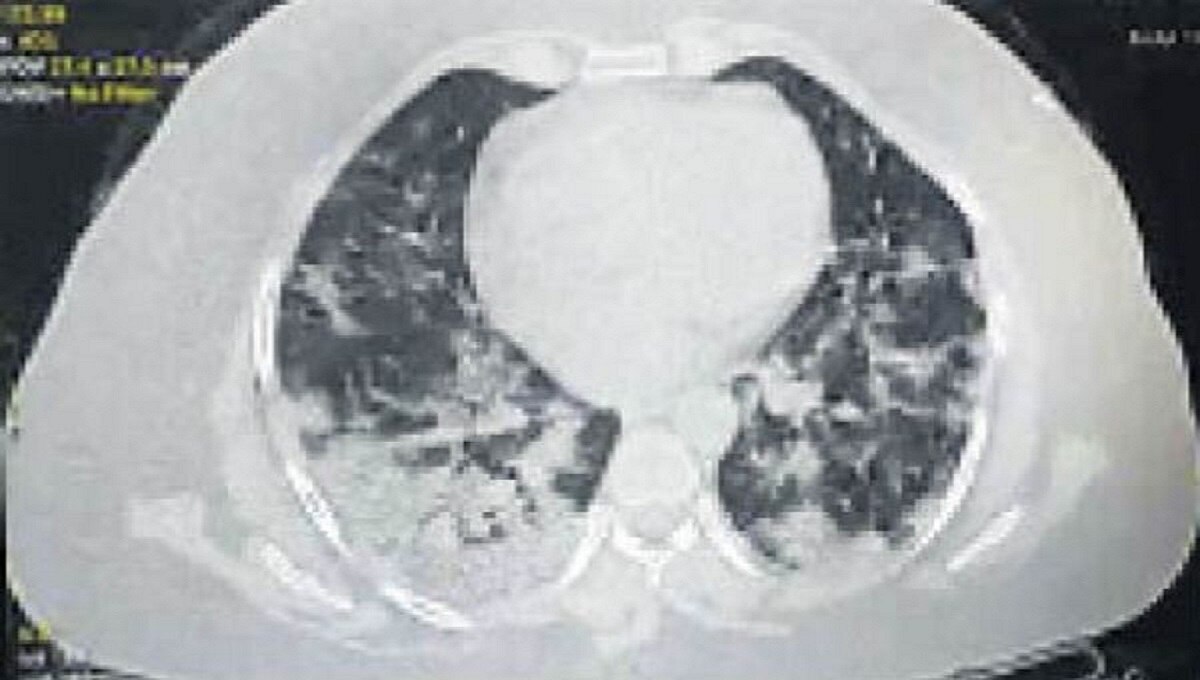

महिला 13 तारीख को खड़ी भी नहीं हो पा रही थी, सांस लेने में दिक्कत हुई तो चेक करने के बाद पता चला कि ऑक्सीजन लेवल 94 था. 13 तारीख को सिटी स्कैन करवाया तो उसके दोनों लंग्स में 80 परसेंट तक इंफेक्शन फैल चुका था.

यह देखकर कोटा के सांस रोग विशेषज्ञ डॉक्टर के के डंग भी चकित रह गए कि मात्र 24 घंटे में लंग्स इतने खराब कैसे हो सकते हैं. उन्होंने इंदौर के विशेषज्ञ डॉक्टर से परामर्श किया. उन्होंने बताया कि यह नया स्ट्रेन है उसी की वजह से ऐसा हुआ है.